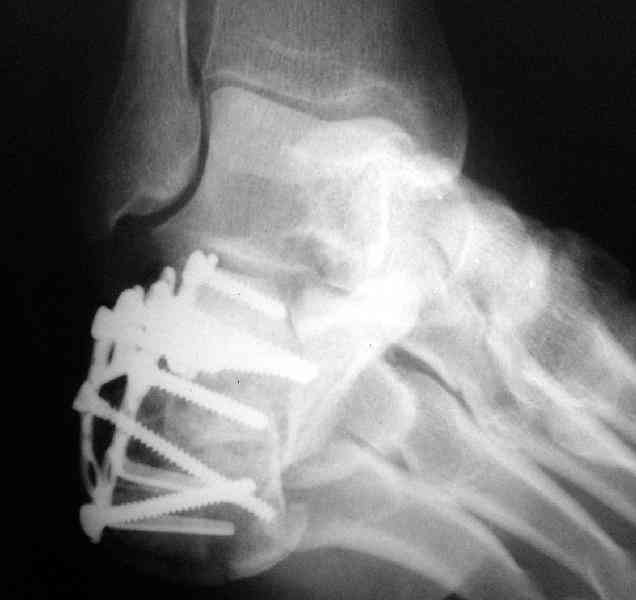

Пяточной пластиной

Открытый и закрытый способы лечения.

MOST OF MY COLLEGUES WOULD OPEN IT LATERALLY( a flap) and having a proper reduction would put a plate.

А хирург спит хорошо, когда пациенту хорошо, и ему не снятся его осложнения.

Имея какой-то опыт остесинтеза пяточной кости пластинами пришли к выводу - где есть альтернатива лучше без нее, где нет значит пластина и долгие переживания в ожидании очередной перевязки. Может нам так не везло, но и одного некроза( слава богу без остеомеилита) достаточно, чтобы призадуматься.

с ув. В Машталов